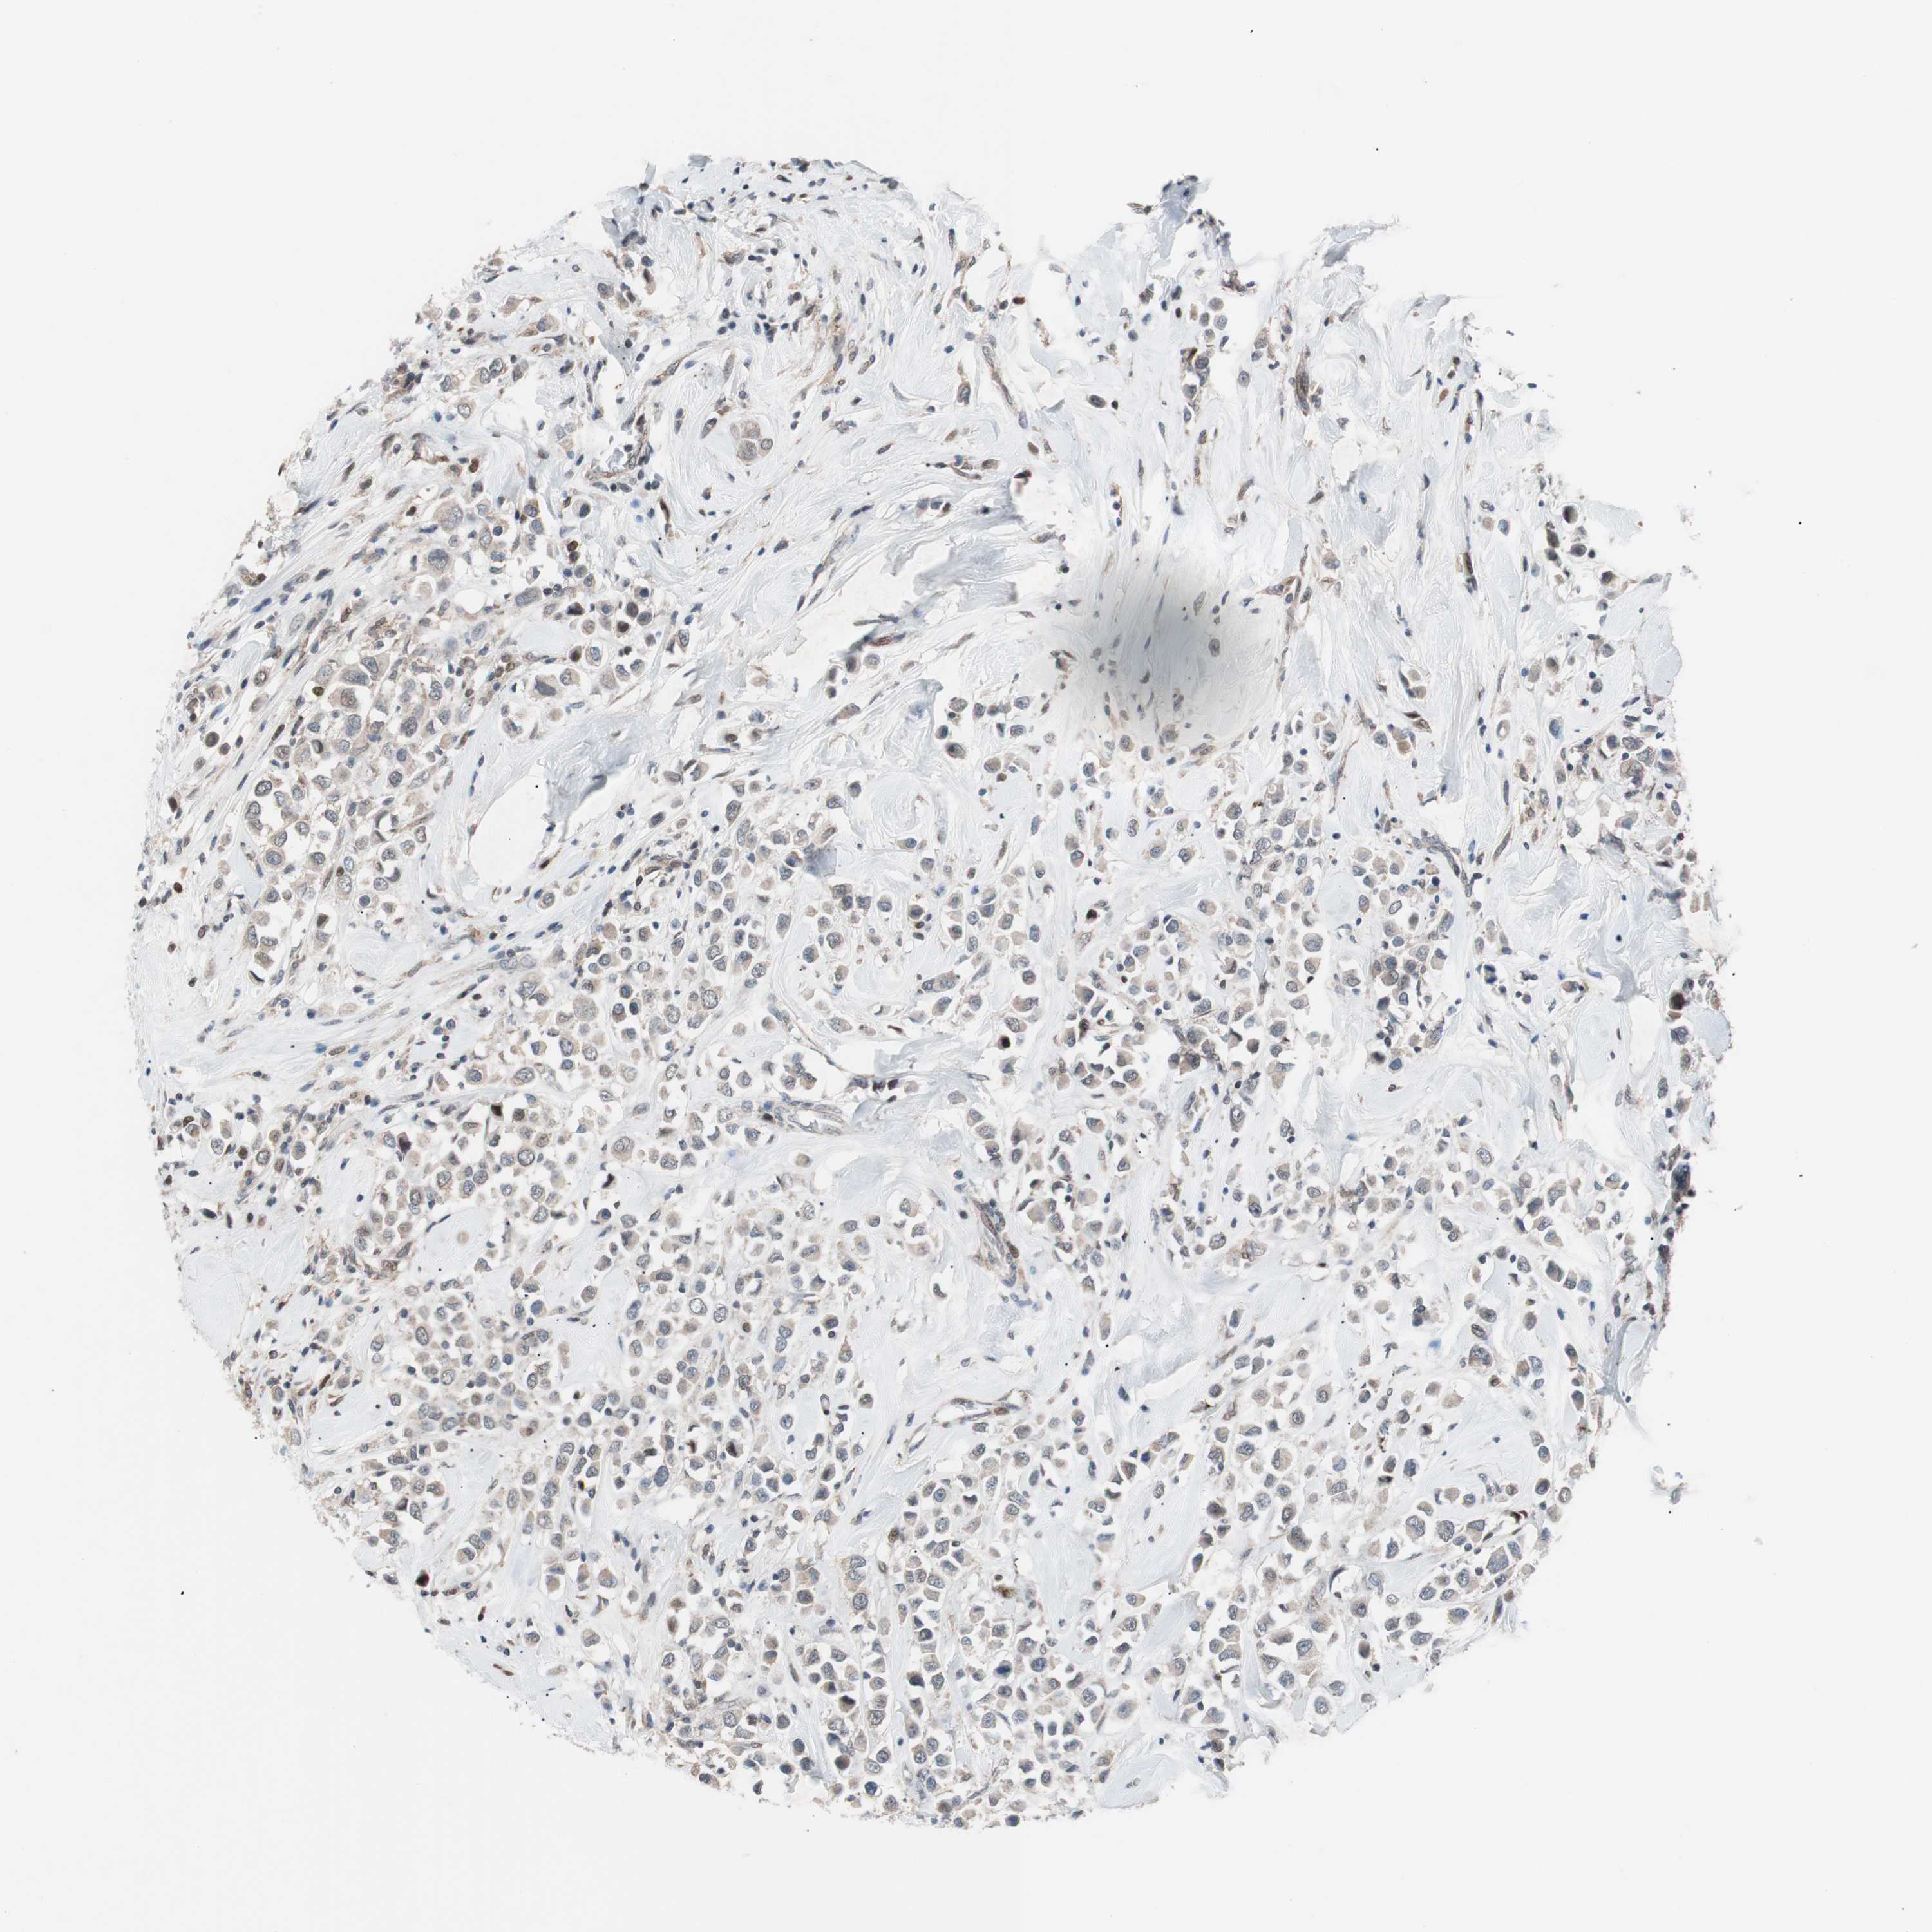

BRCA TCGA BRCA VALIDATION PROTEIN EXPRESSION

ANTIBODIES

AND

VALIDATION